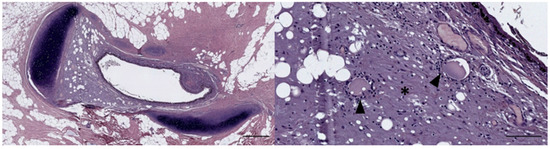

3.1. Ear Canal-Associated Lymphoid Tissue (ECALT)

4.1. Ear Canal-Associated Lymphoid Tissue